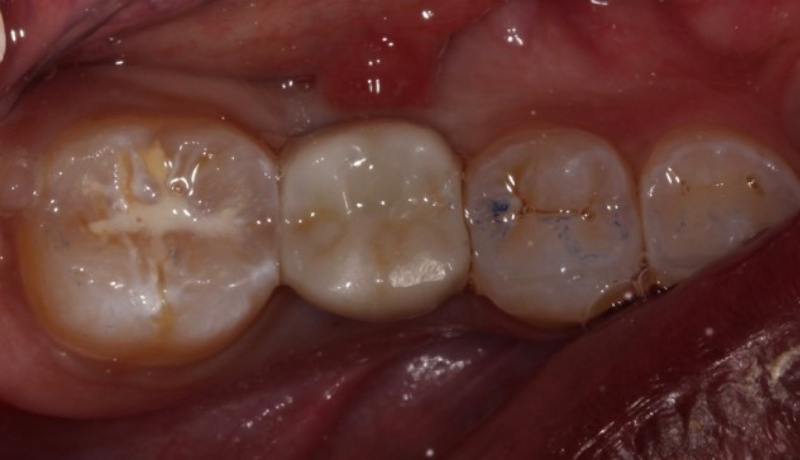

However, cement-retained implant crowns can present challenges if cement is not effectively removed. This is especially true for prefabricated abutments, where the margins can be millimeters subgingival. Multiple studies have demonstrated that patients with cement-retained implant crowns with excess cement are at a higher risk of developing peri-implantitis.

Dr. Chandur Wadhwani, a Seattle-area prosthodontist, demonstrated how excess implant cement can lead to inflammation around implants, contributing to bone loss and peri-implantitis3. As a result, it is advised to design implant crown margins to remove excess cement and take a post-cementation radiograph to determine if excess cement remains after delivering a cement-retained implant crown.

Dr. Georgios Kotsakis, a University of Texas Health Science Center School of Dentistry faculty member, suggests designing implant crown margins that do not extend more than 1.0 mm subgingivally and considering using zinc oxide eugenol or zinc phosphate cement rather than a resin-based cement. Resin-based cements may experience greater biofilm accumulation than zinc oxide eugenol or zinc phosphate cements, leading to a significant risk of inflammation around the implant restoration2.